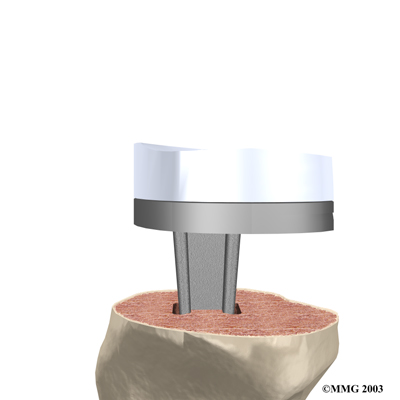

The metal tray that holds the plastic spacer is then attached to the top of the tibia. This metal tray is either cemented into place, or held with screws if the component is of the uncemented variety. The screws are primarily used to hold the tibial tray in place until bone grows into the porous coating. (The screws remain in place and are not removed.)

The plastic spacer is then attached to the metal tray of the tibial component. If this component should wear out while the rest of the artificial knee is sound, it can be replaced. The replacement procedure is called a retread.

View animation of inserting the tibial component: